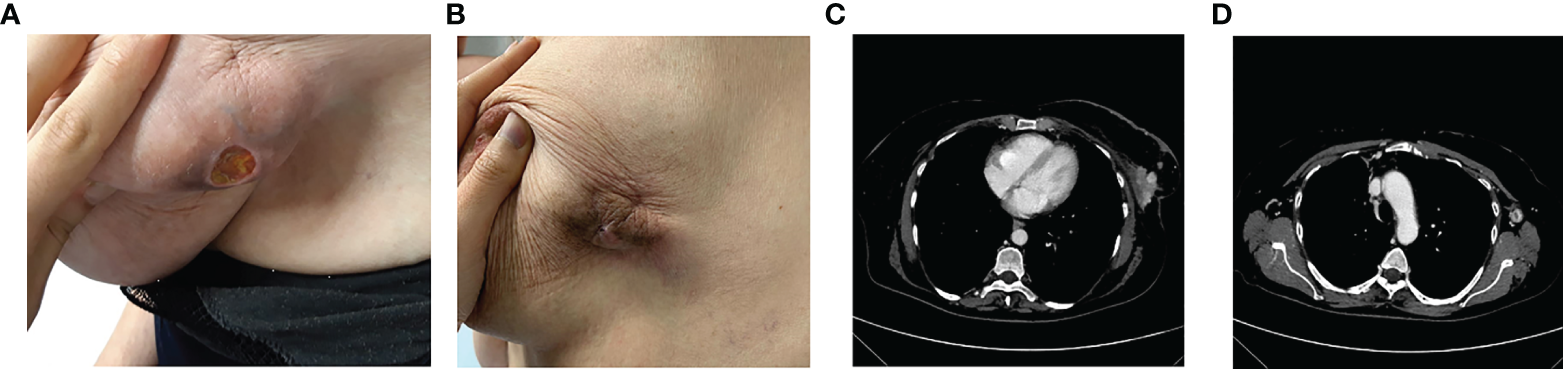

In March 2020, at the first oncological examination she reported a new solid mass in the right breast of about 12 cm, ulceration, and bleeding (Figure 3A) with tumefactions of axillary lymph nodes (DM = 5 cm) and subcutaneous satellite nodules. Right-breast biopsy diagnosed an IDC, ER = 90% PR = 90% ki67 = 20% HER2 = 1+ at the IHC evaluation.

Figure 3

Clinico-radiological presentation of solid, cancer mass of the breast at the diagnosis (A, B), and after 5 months of treatment (C, D).

In April, the CT scan described the presence of a large solid lesion in the right breast of 129 × 42 × 50 mm that infiltrates posteriorly the pectoral muscles, and two lymphadenopathies of 5 × 3 cm in diameter along the axillary extension with no other secondarisms (Figure 3B).

The patient also underwent a bone CT scan, which confirmed the absence of any bone lesions, and a tumor marker blood test (CEA = 18 ng/ml Ca15.3 = 95 U/ml). For the locally advanced, inoperable disease, in May 2020 she started a first-line treatment with ribociclib and fulvestrant. During treatment, she reported clinical response with evidence of more than 30% of reduction in the dimension of the tumor in the right breast (Figure 3C). Taking into account the further radiological response (Figure 3D), the local breast unit discussion concluded that surgery of primary tumor with flap reconstruction became amenable. Thus, the patient underwent mastectomy followed by ribociclib and fulvestrant resumption, which is still ongoing.